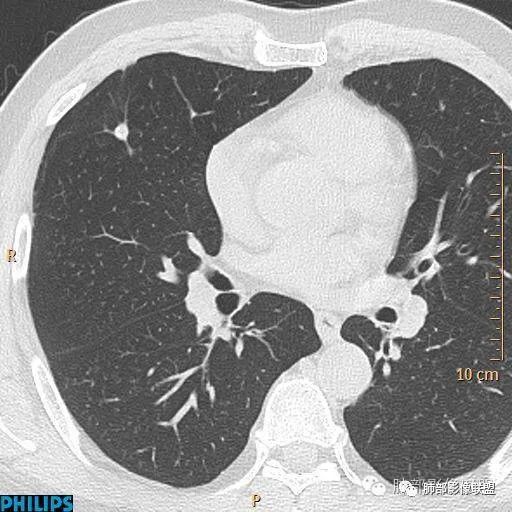

病例二:

正常情况下,肺内淋巴结是不显示的,一般是慢性炎症所致,老年人和吸烟者多见。影像上常见于胸膜或叶间胸膜下,迄今为止,所有的报道均距胸膜或叶间胸膜小于2.0cm以内。也可以表现为与胸膜或叶间胸膜相贴的结节。绝大多数位于中下叶(气管隆突水平以下),上叶也可见到,但较少见。

长径均小于12mm。典型的形状为三角形,也可以为梭形、圆形或椭圆形。诊断的关键在于见到1-5条细线与胸膜、叶间胸膜或静脉相连,有时状如坐落于电路板的“二极管”,但以薄层CT显示为佳。有作者病理对照线状影为小叶间隔,有作者病理对照为淋巴管。其实不矛盾,因为淋巴管走行于小叶间隔内。